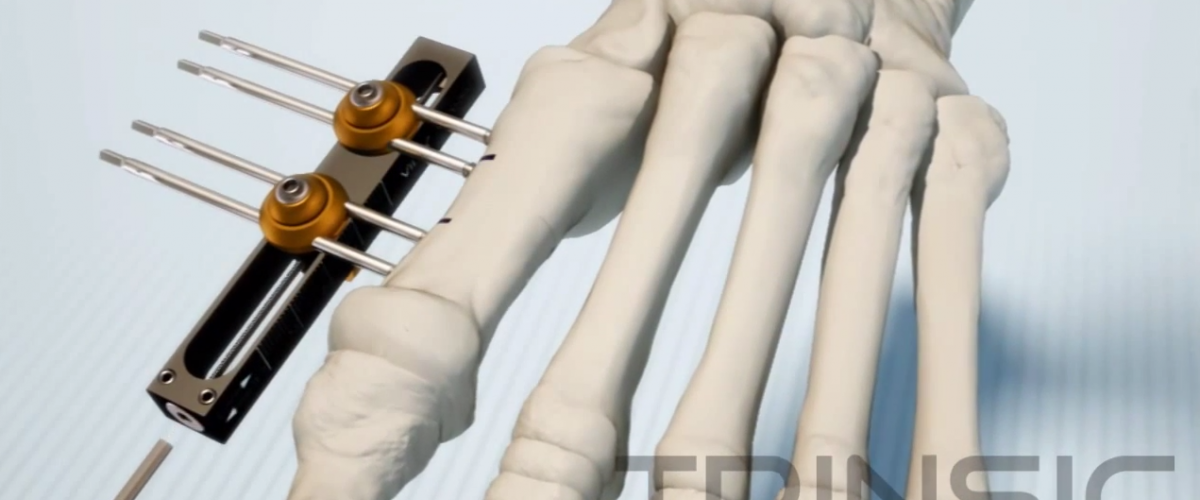

Vilex mini rails are external fixators used in hand and foot surgeries .They are ideal for revision of a failed surgery for example mal or non-union distraction of an impacted joint or bone lengthening using ocio genesis to name a few.